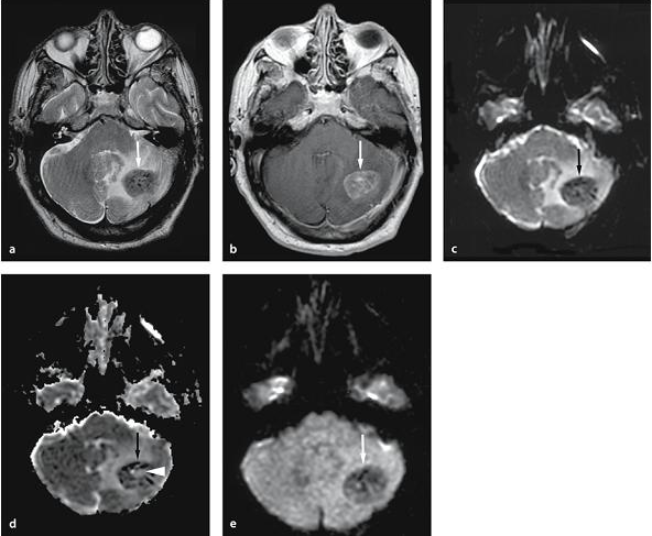

Những hình ảnh thu được từ chụp cộng hưởng từ MRI luôn cho độ phân giải cao và có thể khảo sát được đa mặt cắt, mang đến những hình ảnh sắc nét, chân thực nhất về vị trí cần chụp, đánh giá thành công những tính chất của mô cần phải khảo sát. Từ đó, mang đến giá trị có lợi cho quá trình chẩn đoán và điều trị của bác sĩ chuyên khoa về tình trạng hiện tại của tĩnh mạch.

- Nhận được những hình ảnh chất lượng, đa mặt phẳng như mặt phẳng dọc, mặt phẳng ngang, mặt phẳng trán và bất kỳ mặt phẳng nghiêng nào khác.

- Độ phân giải của mô mềm tương đối cao.

- Chất lượng hình ảnh hiển thị tốt hơn so với các phương pháp chụp thông thường.

- Có khả năng chụp được những mạch máu Não (MRA), ngay cả khi không sử dụng thêm những chất tương phản cần thiết.